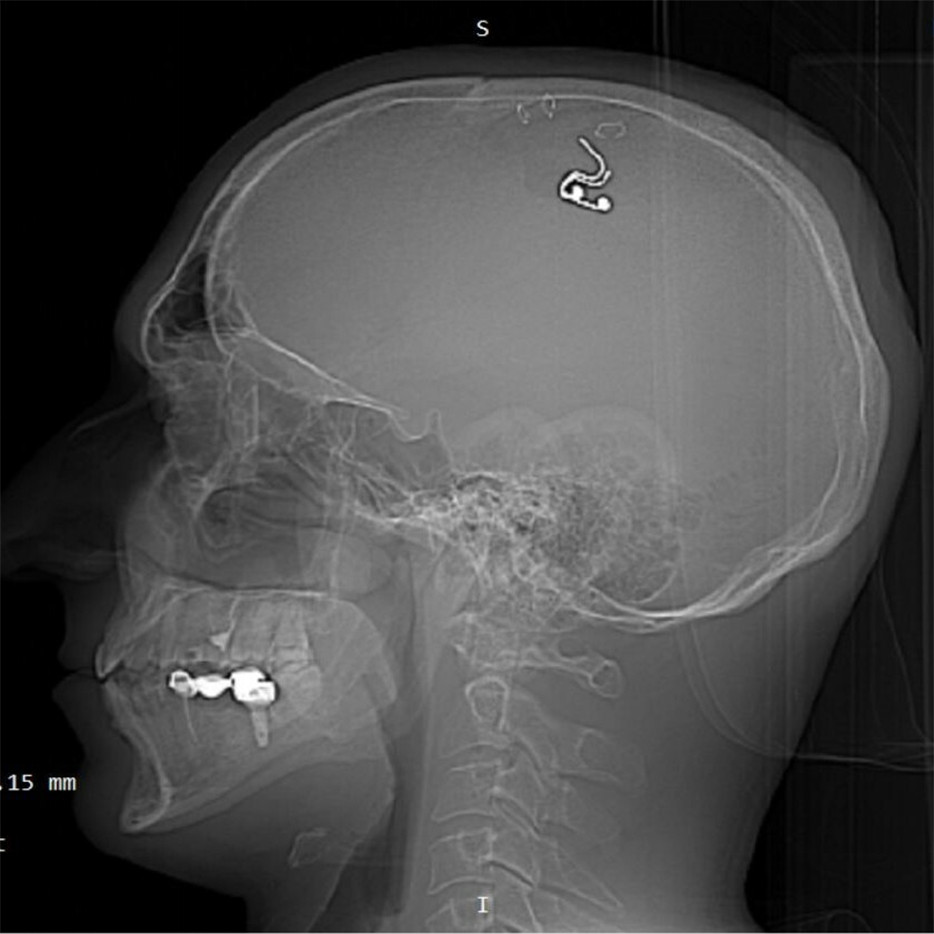

20/07/2023 01:22Nhà khoa học Nga gây sửng sốt vì tuyên bố tự phẫu thuật não tại gia

Michael Raduga, nhà nghiên cứu người Nga không có bằng cấp về phẫu thuật thần kinh, kể ông đã mất hơn 1 lít máu khi tự thực hiện ca phẫu thuật cấy ghép một điện cực vào não tại phòng khách nhà riêng ở Kazahstan.

Ông Raduga tiết lộ, mục đích của cuộc phẫu thuật là giúp ông một ngày nào đó có khả năng kiểm soát những giấc mơ của mình.

Bản thân ông Raduga thừa nhận, khoảng 30 phút sau khi bắt đầu tự phẫu thuật, ông đã sẵn sàng bỏ cuộc vì mất rất nhiều máu và sợ mình có thể bất tỉnh. Tuy nhiên, ông nói bản thân cuối cùng vẫn hoàn thành ca phẫu thuật, tắm rửa và làm việc trong khoảng 10 giờ liên tục mà không ai nhận ra những gì ông đã làm.

Nhà nghiên cứu Nga cũng không nói với ai về kế hoạch tự phẫu thuật của mình. Thay vào đó, ông chuẩn bị bằng cách xem hàng giờ cảnh phẫu thuật não trên YouTube và thử nghiệm trên một vài con cừu.

Khoảng 5 tuần sau ca tự phẫu thuật, ông Raduga phải vào bệnh viện để các bác sĩ lấy điện cực ra khỏi não của mình. Tuy nhiên, theo kênh Telegram của Trung tâm Nghiên cứu giai đoạn, ông vẫn đang tìm kiếm những người “sẵn sàng cấy ghép não để có giấc mơ sáng suốt, hiệu quả hơn”.